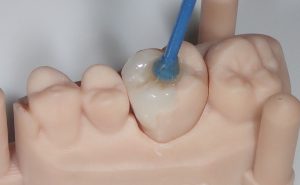

carie vue grâce au « carie detector »